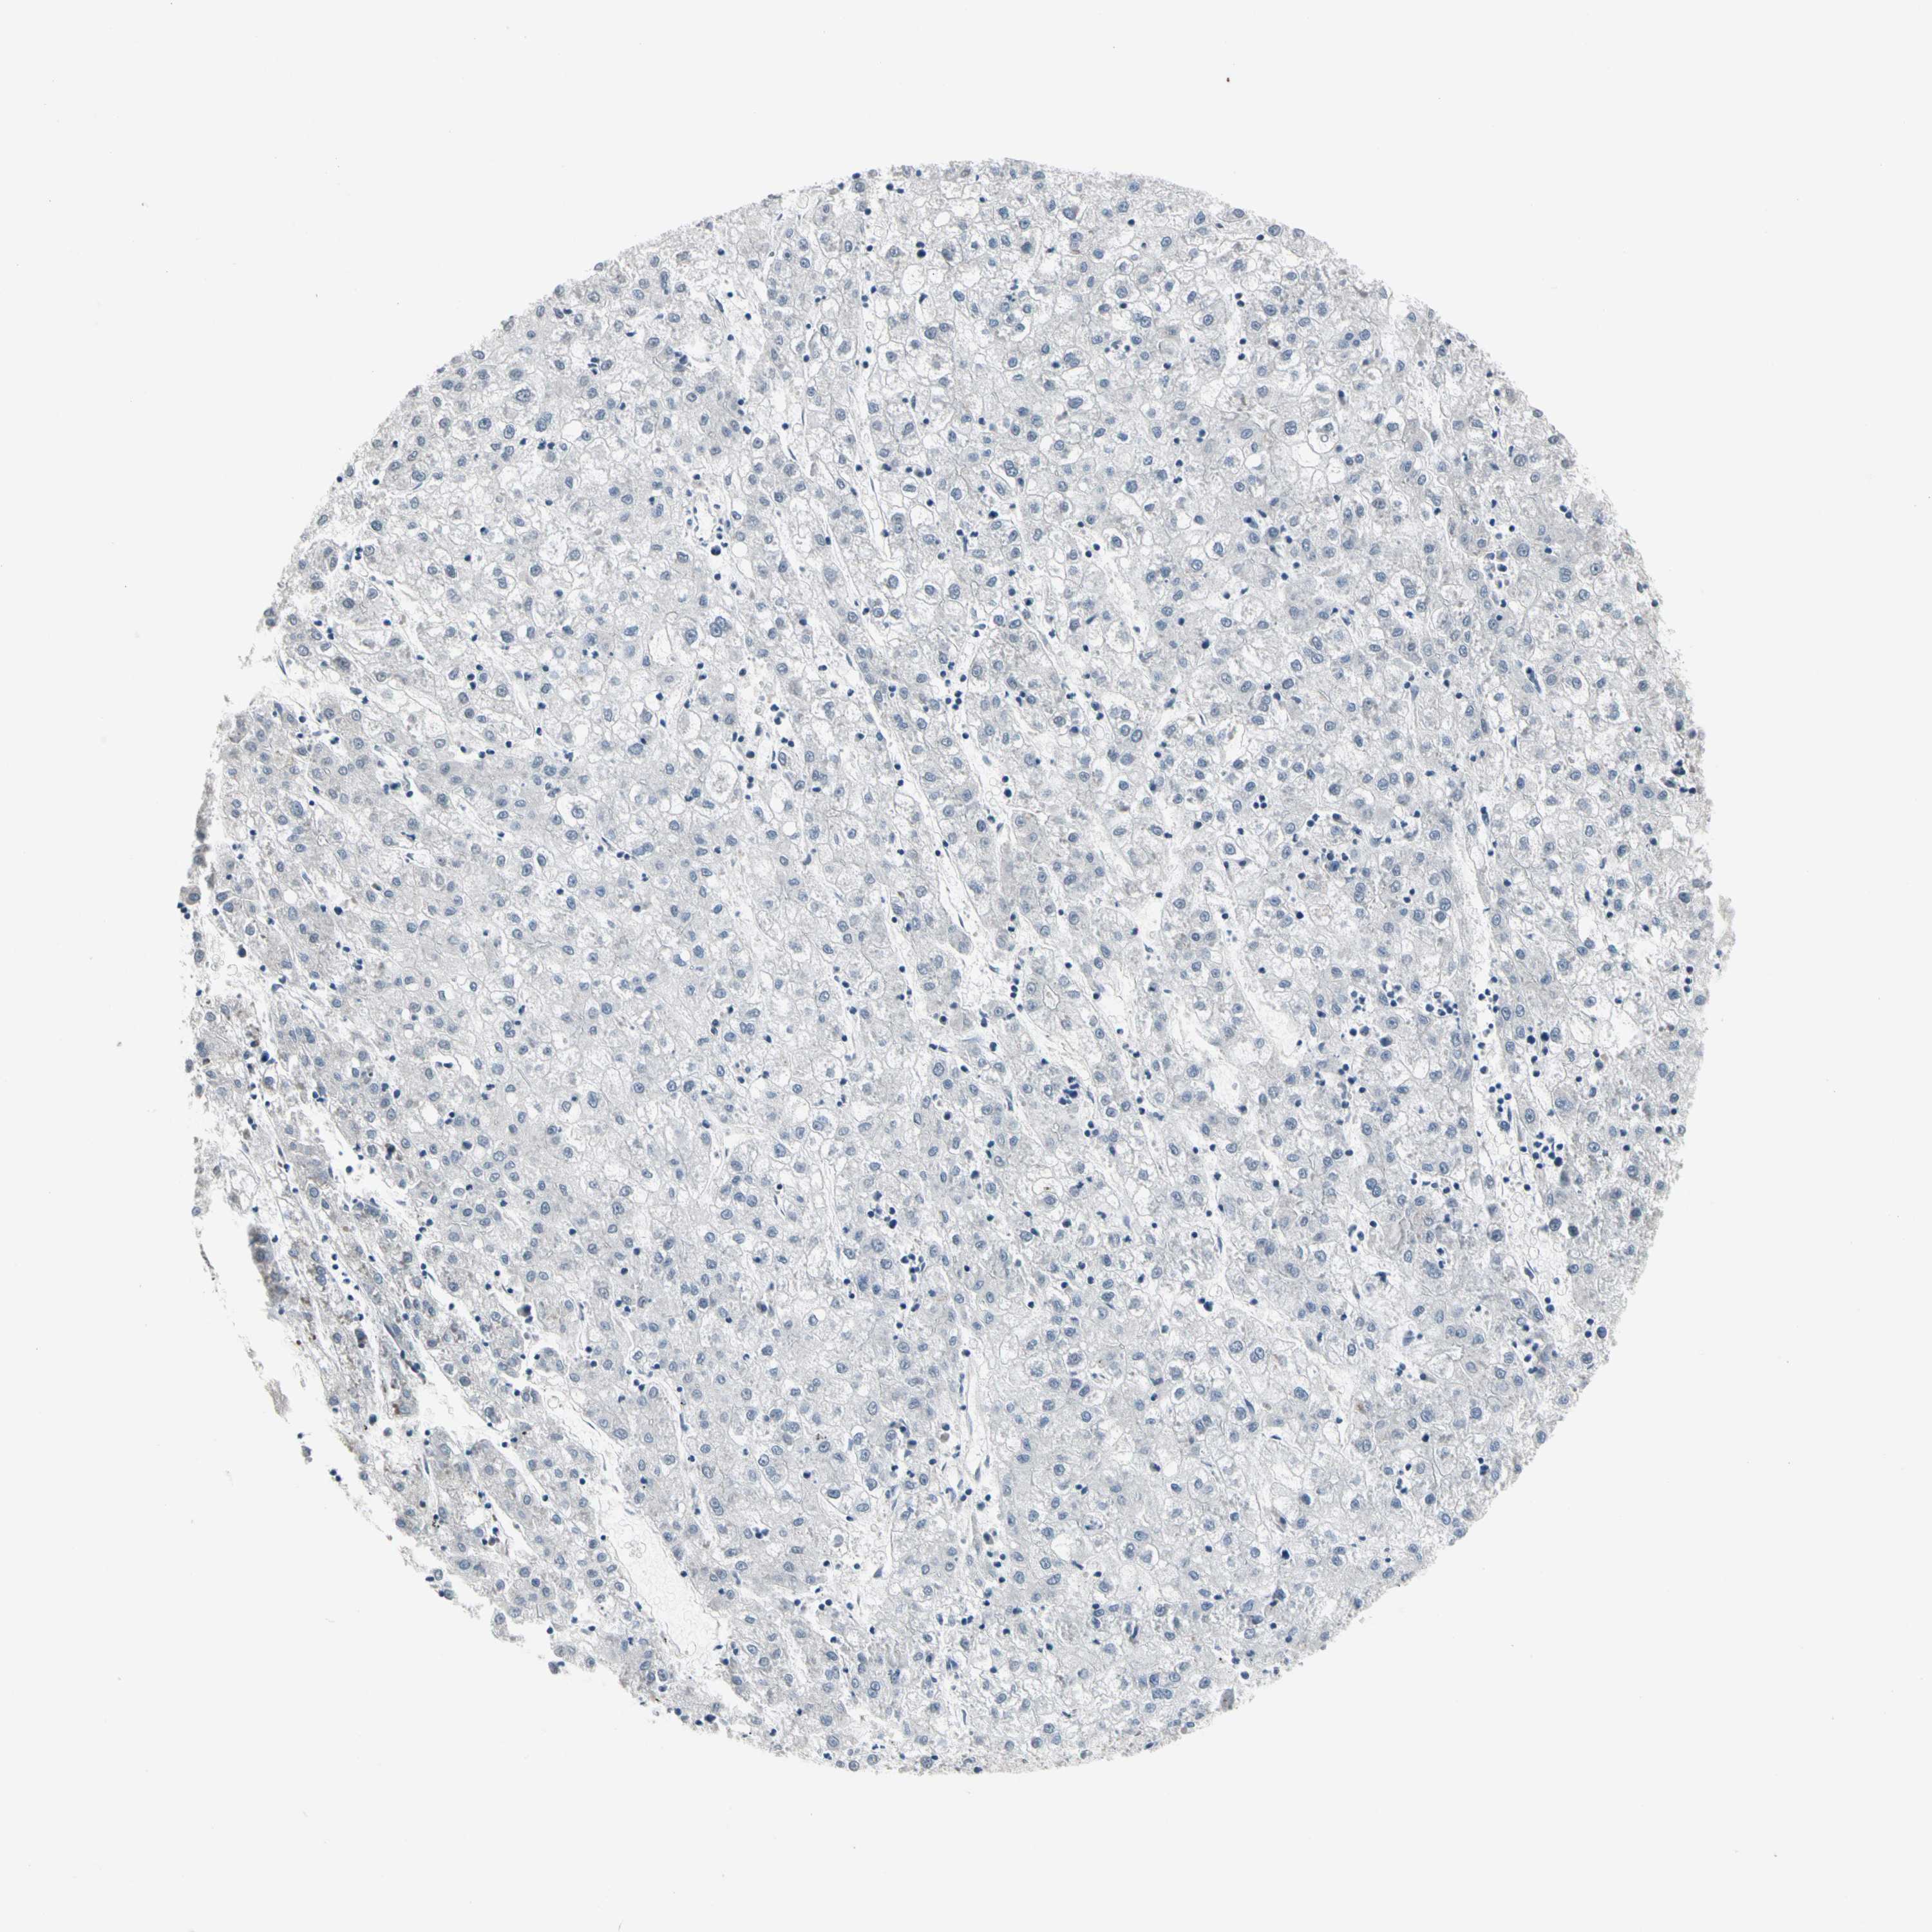

LIVER CANCER - Protein expressioni

A mouse-over function shows sample information and annotation data. Click on an image to view it in a full screen mode. Samples can be filtered based on level of antibody staining by selecting one or several of the following categories: high, medium, low and not detected. The assay and annotation is described here.

Note that samples used for immunohistochemistry by the Human Protein Atlas do not correspond to samples in the TCGA dataset.

Antibody stainingi

Antibody staining in the annotated cell types in the current human tissue is reported as not detected, low, medium, or high, based on conventional immunohistochemistry profiling in selected tissues. This score is based on the combination of the staining intensity and fraction of stained cells.

Each image is clickable and will lead to virtual microscopy that enables deeper exploration of all samples and also displays staining intensity scores, fraction scores and subcellular localization as well as patient and tissue information for each sample.

Antibody HPA007863

Antibody CAB002226

Staining

High

Medium

Low

Not detected

Intensity

Strong

Moderate

Weak

Negative

Quantity

>75%

75%-25%

<25%

None

Location

Nuclear

Cytoplasmic/membranous

Cytoplasmic/membranous,nuclear

Cholangiocarcinoma

Carcinoma, Hepatocellular, NOS